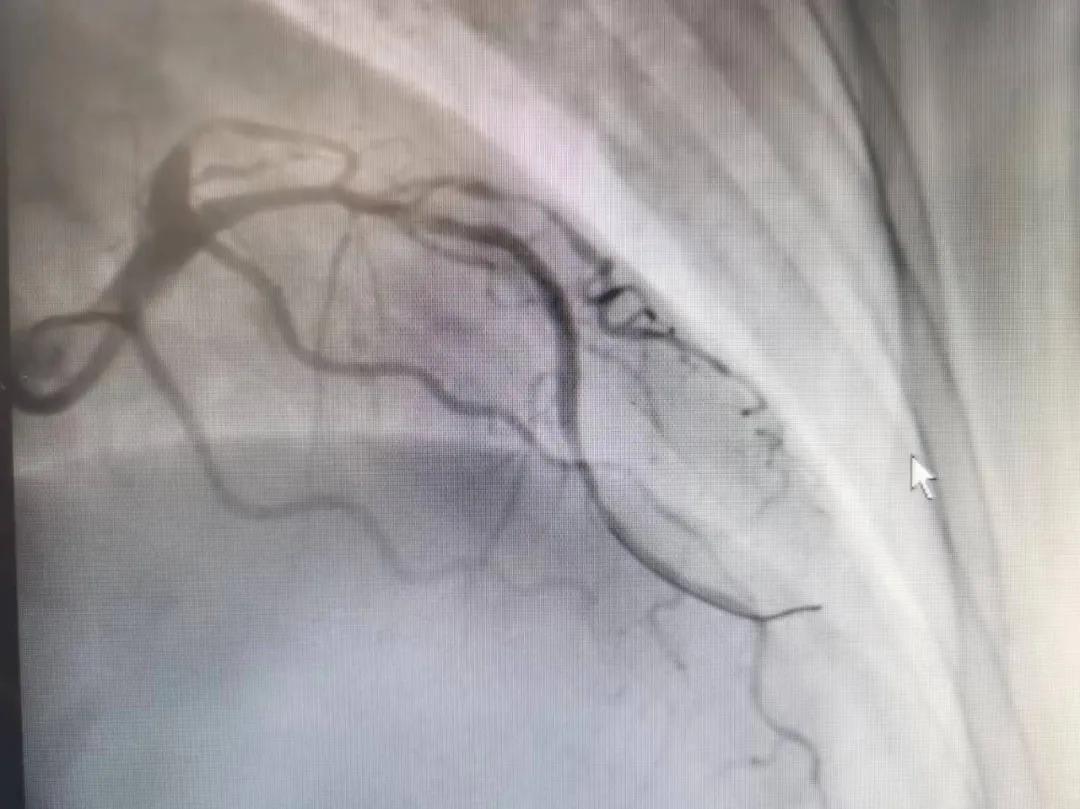

病人是位六十多歲的女性患者,有長期高血壓病史,1個月前開始出現(xiàn)胸悶胸痛,口服藥物治療效果不佳,經(jīng)朋友介紹,來到市二院心血管內(nèi)科。入院后完善冠狀動脈造影提示:前降支全程彌漫性狹窄伴鈣化,最重95%,回旋支狹窄約85%,右冠脈全程狹窄伴鈣化,最重60%。血管內(nèi)超聲顯示右冠脈開口面積3.36mm²,可見環(huán)形鈣化,考慮患者病變程度重、鈣化明顯,常規(guī)器械無法實現(xiàn)病變的良好預處理,且有很高的冠脈穿孔、血管夾層的風險。

術前